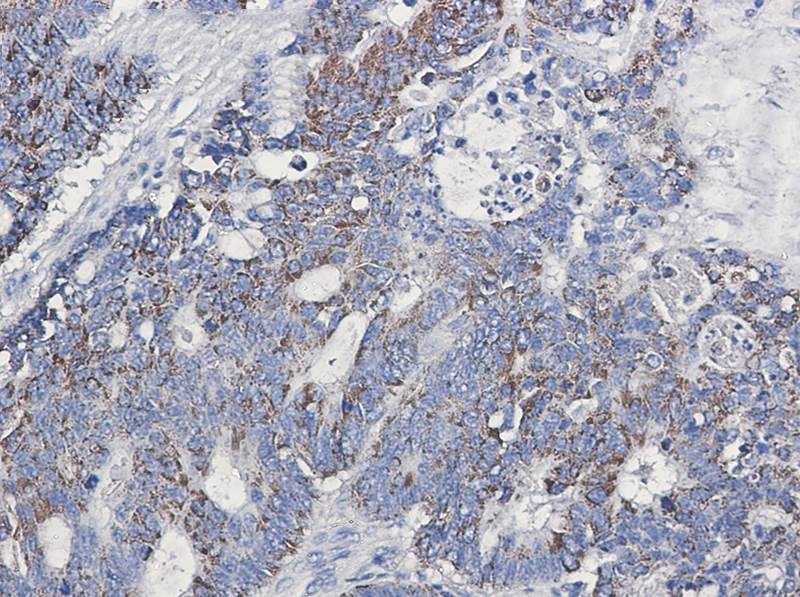

Immunohistochemistry of CD147 in paraffin-embedded Human colon cancer tissue using CD147 Rabbit mAb at dilution 1/50